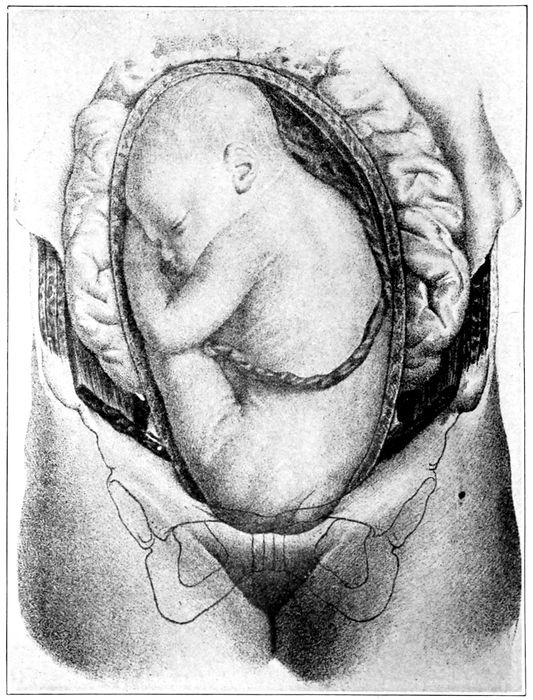

Child in second stage of labor |

116 |

| |